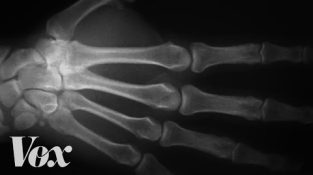

Sta se desi sa prstima kada ti Cracker?

Један човек је 60 година ломио зглобове на једној руци, а на другој не. Pogledajte i video da vidite šta je saznao.